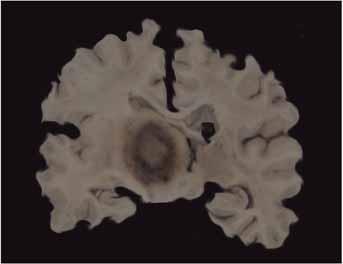

Obrázek 1.

Prokrvácený primární lymfom mozku infiltrace bazálních

ganglií.